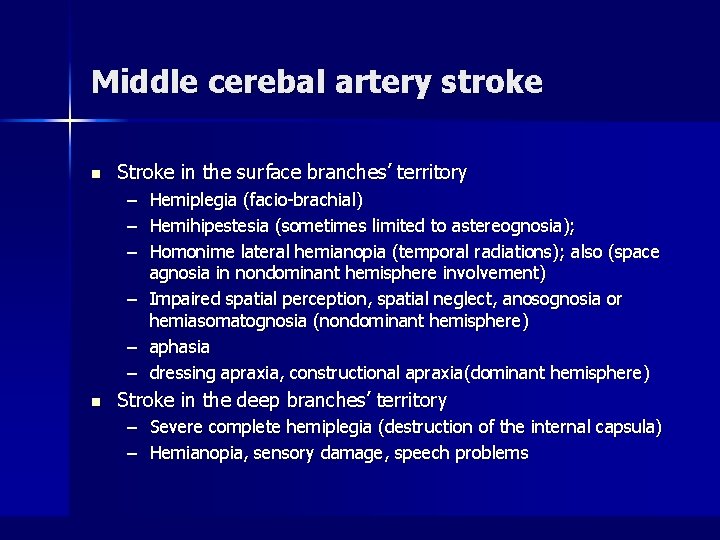

Middle cerebal artery stroke n Stroke in the surface branches’ territory – – – Hemiplegia (facio-brachial) Hemihipestesia (sometimes limited to astereognosia); Homonime lateral hemianopia (temporal radiations); also (space agnosia in nondominant hemisphere involvement) – Impaired spatial perception, spatial neglect, anosognosia or hemiasomatognosia (nondominant hemisphere) – aphasia – dressing apraxia, constructional apraxia(dominant hemisphere) n Stroke in the deep branches’ territory – Severe complete hemiplegia (destruction of the internal capsula) – Hemianopia, sensory damage, speech problems